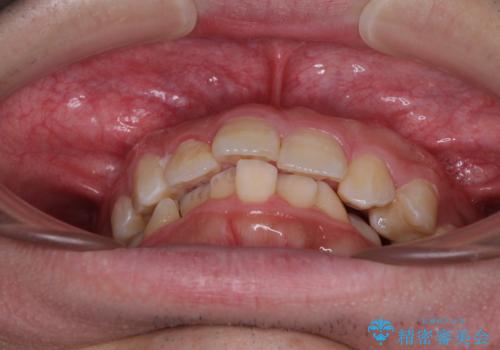

骨格的に、下顎が右側にずれており、左側の咬み合わせに鋏状咬合などのアンバランスが生じている状態でした。

また、上顎前歯に欠損が1本あり、上下ともに前歯部に叢生が認められ、下顎前歯の大半が隠れてしまうほどの過蓋咬合も認められました。